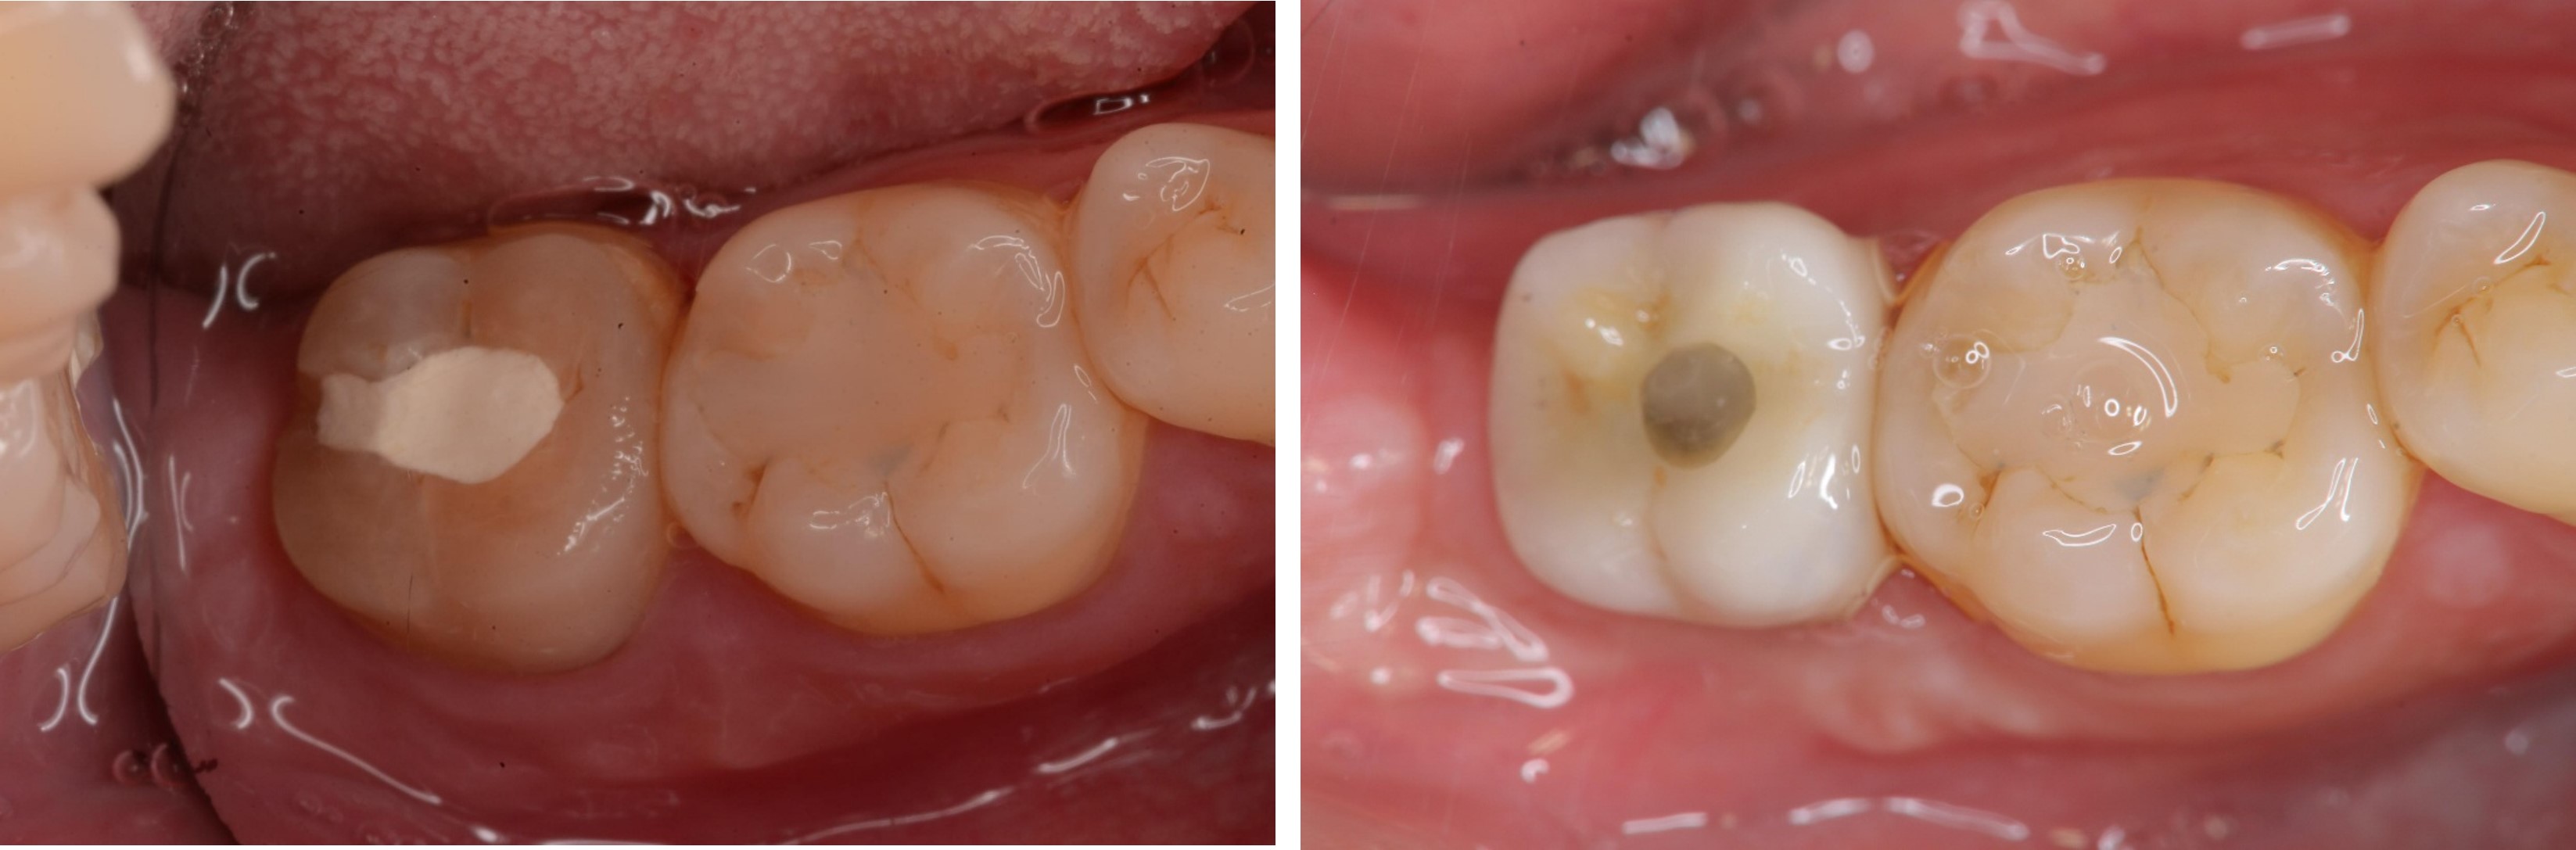

拔牙後進行骨脊保存術

植牙前口內評估